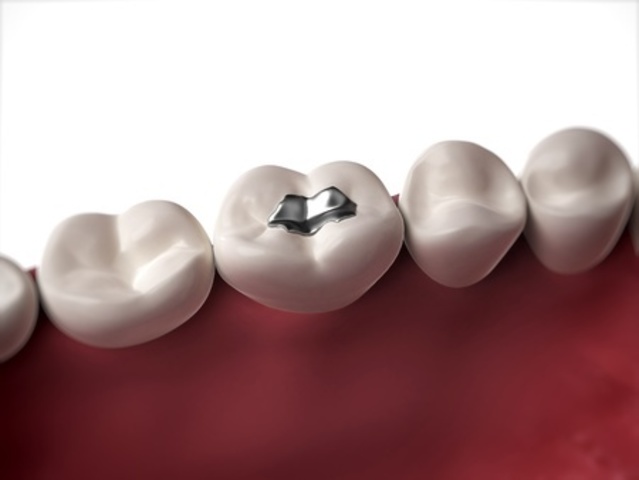

La amalgama de plata para obstrucciones es usada por primera vez por el Dr Thomas W. Evans.

Se realiza la mejora en el diseño de amalgamas usando compuesto de un 68% de plata por G.B. Black.